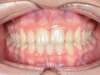

Cas 3 : Description

Recouvrement incisif important, Manque d’espace. Traitement multibague sans extraction.

Avant

Après